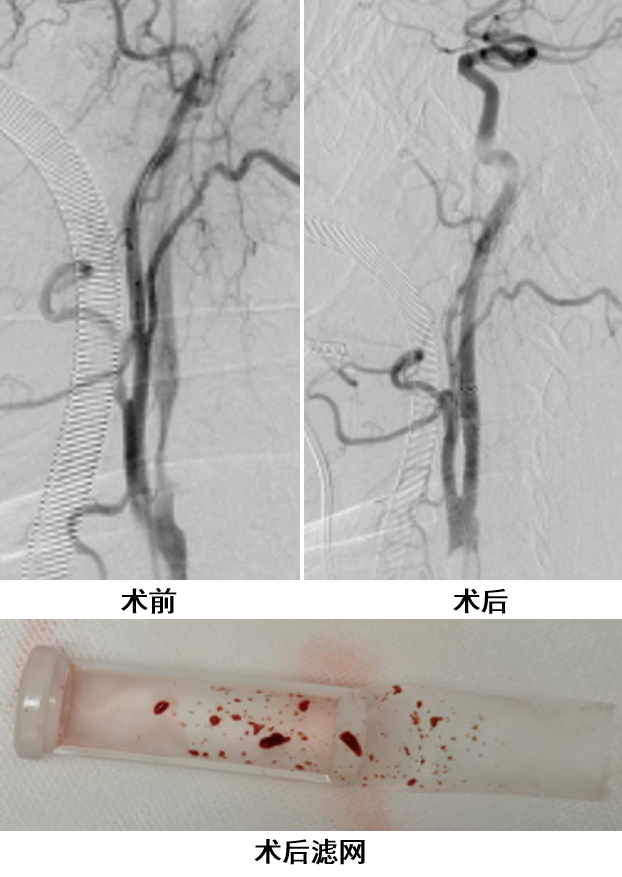

病例三

颈动脉次全闭塞,斑块负荷重且为软斑,行传统CAS时保护伞通过困难,卒中风险陡增。

在这些“两难”的复杂情境下,PT-CAS凭借其直接入路、无盲区保护的优势,为患者提供了安全有效的治疗方案,更值得注意的是,术中滤网成功捕获了大量肉眼可见的斑块碎屑,甚至包括大块残渣,这直接证明了该技术在处理高风险、富含软斑的重度狭窄病变时,其脑保护机制的有效性。